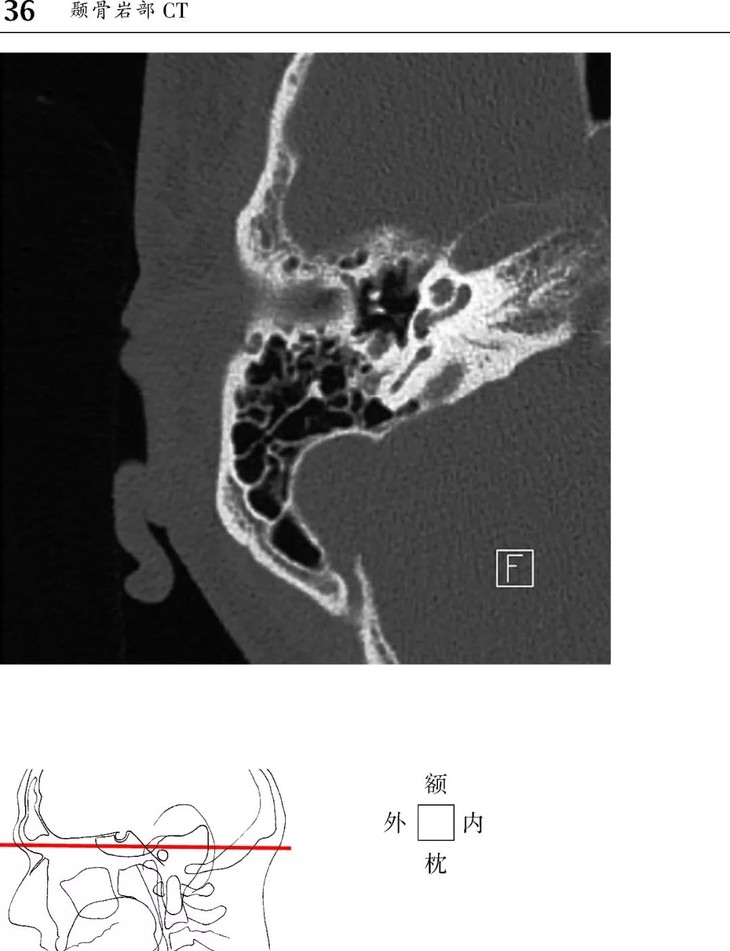

1、头部CT图像新增轴位和冠状位颞骨图像。

本书为断层解剖图谱,包括头颈部断层解剖,还包括脑部血管造影术,每一层面都包括精确的断层解剖和对应的彩色插图,左边页面为CT/MR图像,右边页面为对应的彩色手绘解剖示意图,便于学习和记忆!

1、版面采用教学式设计,2页为一个单元,左边页面为CT/MR图像,右边页面为对应的彩色手绘解剖示意图,并一一注明了解剖部位。

2、几百幅高清的CT/MR图片,对解剖结构显示更加清晰,其中许多图片都是采用最新的设备扫描的,如3.0T MRI,64层CT。